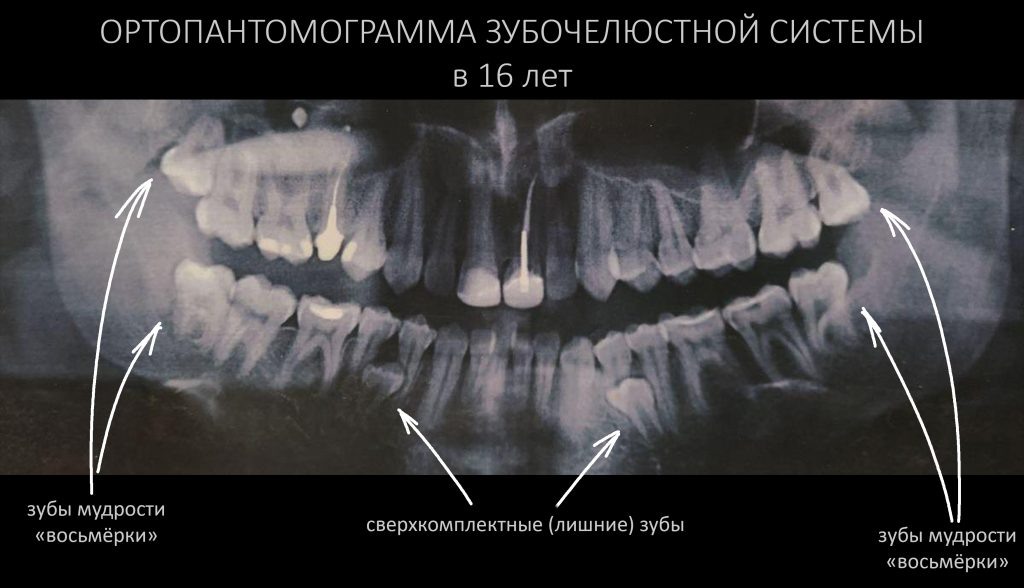

История Александра находится здесь>>, и мы очень рекомендуем её прочитать. Для вашего удобства мы не перепечатываем её вновь. Вместо этого, мы выбрали из неё достойные пояснения и ремарок цитаты: они выделены вот таким образом и снабдили их уместным, на наш взгляд, комментарием. Пользуясь случаем, мы еще раз благодарим Александра, за прекрасное и честное описание своего лечения , а также предоставленную возможность дать к нему пояснения. *    *    * В 16 лет я увидел панорамный снимок (фото ниже) и, уже успев натерпеться стоматологии и врачей,

я побежал, споткнулся и выбил передние зубы о бетонную плиту). На ортопантомограмме зубочелюстной системы 16-летнего Александра мы видим почти полностью сформированные восьмёрки и сверхкомплектные зубы. Понятное дело, что появились они не месяц и не два назад, их зачатки можно было бы увидеть на снимках 2-3 года назад. Эти самые

В 16 лет я увидел панорамный снимок (фото ниже) и, уже успев натерпеться стоматологии и врачей,

я загрустил (я только что сильно болел фронтитом и гайморитом в 15 лет, в 7 классе только перестав носить пластинку,

я побежал, споткнулся и выбил передние зубы о бетонную плиту).

На ортопантомограмме зубочелюстной системы 16-летнего Александра мы видим почти полностью сформированные восьмёрки и сверхкомплектные зубы. Понятное дело, что появились они не месяц и не два назад, их зачатки можно было бы увидеть на снимках 2-3 года назад. Эти самые зачатки (или зубы с незавершенным формированием корневой системы) удаляются намного проще и безопаснее, чем полноценно сформированные зубы – вот почему мы рекомендуем, начиная с периода смены прикуса (7-14 лет) посещать стоматолога и проводить диагностическую ортопантомографию хотя бы раз в год. Раньше выявили проблему = раньше её решили = меньше последствий = дешевле.